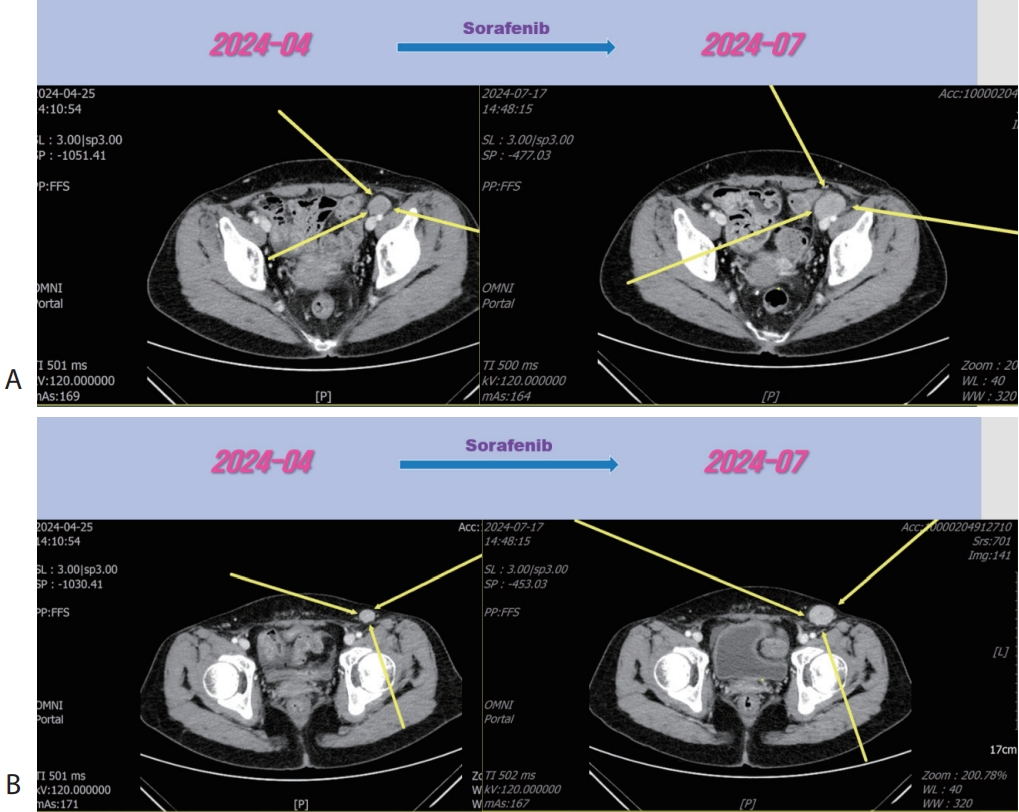

Figure 5.Liver CT scan (A, B) after 3rd line regorafenib therapy. Pelvic (A) and inguinal (B) lymph node metastasis were slightly increased after regorafenib therapy. CT, computed tomography.

Figure 6.Liver CT scan (A, B) after combination therapy of RT and 3rd line regorafenib. Slightly increasing pelvic (A) and inguinal (B) lymph node metastasis were marked shrinked after combination therapy. CT, computed tomography.

®, 40 mg per dose; Bayer) for 3 months and LN metastasis was slightly increased (

Fig. 5), then we decided to combine RT for LN metastasis (40 Gray/16 fraction). Then the LN metastasis was markedly decreased (

Fig. 6). We are keeping on treating the patient with regorafenib therapy for over 12 months. We summarized treatment timeline of patient (